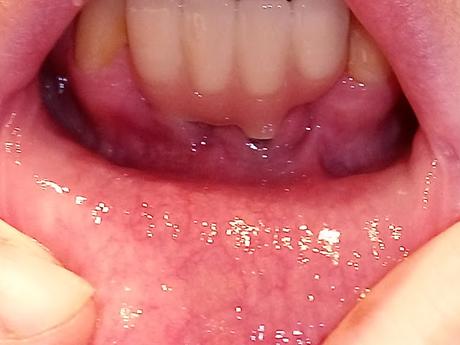

Se trata de un enrojecimiento y/o inflamación de las encías, debido a la presencia de una infección por bacterias (Porphyromonas gingivalis).

Es la primera fase de la enfermedad periodontal.

- Inflamación y enrojecimiento de las encías.